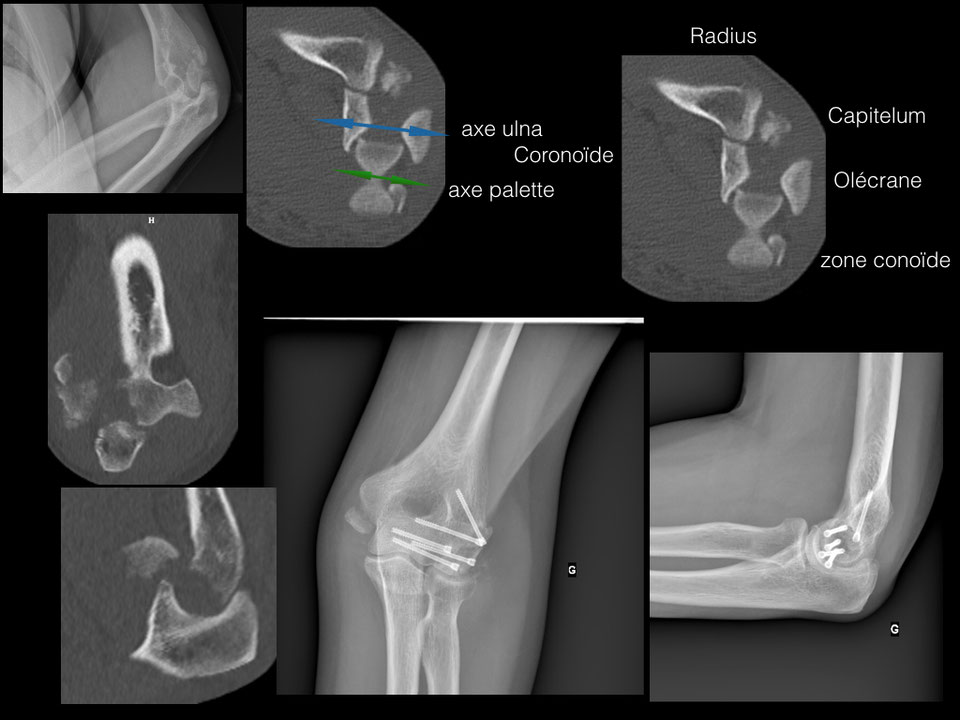

Fractures du COUDE Fractures distales de l humérus Fracture Coude Traitement La fracture du coude désigne le plus souvent la fracture de la parte inférieure de l’humérus, qui est l’os du bras. Le traitement des fractures de l’olécrane repose sur le port d’une attelle, parfois une chirurgie et un traitement par antibiotiques en cas de fracture. Une fracture du coude est une rupture d’un ou plusieurs des os qui constituent l’articulation. Fracture Coude Traitement.